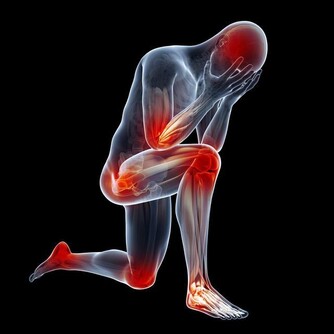

●膝蓋退化了沒!中醫師蔡曜鍵教你自行檢測,還要提供養膝茶飲!還 不快抄起來。